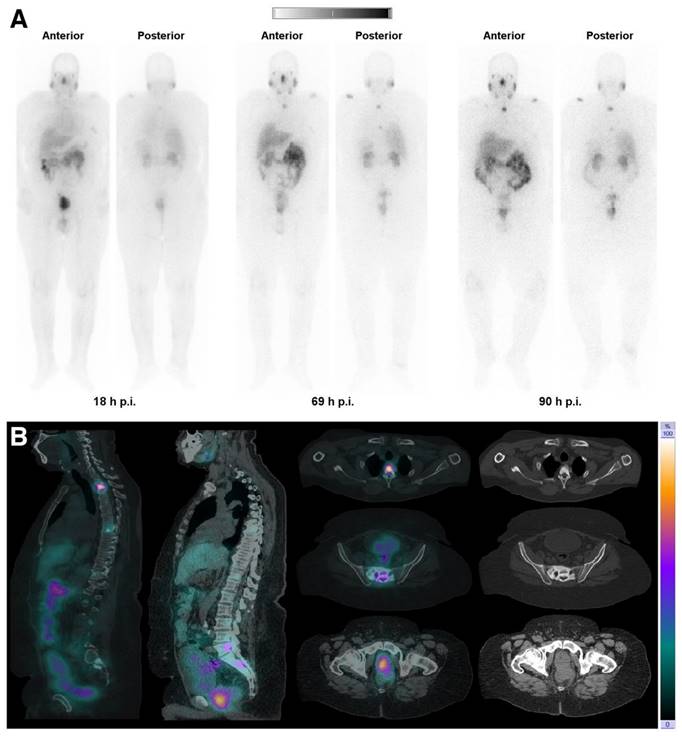

The feasibility of SPECT imaging through the γ-ray emission of terbium-161 has also been thoroughly investigated [13,15,81,93]. Interestingly, the first-in-human SPECT/CT imaging using [161Tb]Tb-DOTATOC and [161Tb]Tb-PSMA-617 showed encouraging results as the obtained images were of good quality and enabled visualization of all the previously identified tumor lesions using [68Ga]Ga-DOTATOC (Figure 14) [95,96]. Dual-isotope SPECT imaging with terbium-161 and lutetium-177 also becomes possible due to the difference in γ-energies, as demonstrated in preclinical studies [15,94]. The simultaneous visualization of these two distinct isotopes also provided further evidence confirming the previously hypothesized interchangeability of these radionuclides without any significant impact on their tissue biodistribution [15,94]. The promising outcomes of this research suggest that future (pre)clinical investigations involving terbium-161 can confidently rely on the preclinical data acquired from its 177Lu-labeled counterpart. This would accelerate research efforts, allowing researchers to directly focus on exploring the therapeutic efficacy of terbium-161, which appears to exhibit superior effects compared to lutetium-177 [15].

Figure 14

(A) Whole-body images at different time points after injection of 5550 MBq of [161Tb]Tb-PSMA-617. (B) Representative SPECT/CT sagittal and axial slices and CT axial slices demonstrating physiologic biodistribution in lacrimal, parotid, and submandibular glands; nasopharyngeal mucosa; liver; intestinal tract; kidneys; and urinary bladder, as well as pathologic uptake in primary prostate tumor and metastatic bone lesions. (p.i. = post-injection). Reprinted with permission from Al-Ibraheem et al. [96], copyright 2023 by the Society of Nuclear Medicine and Molecular Imaging.

[161Tb]Tb-PSMA-617PeptideSPECT/CT images were obtained 18-69-90 h p.i. of 5,550 MBq conjugateThe obtained images were of good quality, enabling visualization of all previously identified PSMA-avid primary and metastatic bone lesions using a [68Ga]Ga-PSMA PET/CT scan. The application of [161Tb]Tb-PSMA-617 was well tolerated, and no related adverse events were reported.Patient with mCRPC, refractory to chemotherapy.[96]